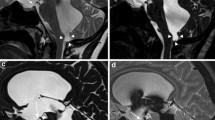

All patients except one were imaged according to our institution’s protocol with propofol anesthesia provided by the anesthesia department on 1.5 T or 3 T scanners (Siemens Magnetom Avanto and Skyra, Siemens Healthineers, Erlangen, Germany). A single patient in the enlarged subarachnoid spaces of infancy group was papoosed without resulting patient motion on the phase contrast sequence. Scans included axial T2 turbo spin echo (2–4 mm slice thickness, 4500 TR, 112 TE, 120 FA 224 × 320 matrix), axial EPI diffusion weighted imaging (3 mm slice thickness 7100 TR, 97 TE, 90 FA, 160 × 160 matrix), and through plane phase contrast imaging performed at the level of the cerebral aqueduct, direction cranial to caudal, Venc = 20 cm/s for one cardiac cycle (24.75 TR, 7.66 TE, 15 FA 256 × 256 matrix) (Fig. 1).

Flow data image analysis

The image analyst (MS) who performed region-of-interest measurements also performed the flow region-of-interest measurements. All images were de-identified and imported into a commercially available cardiovascular imaging software (cvi42, 5.14 Circle Cardiovascular Imaging, Calgary, Canada). The phase contrast images were used for segmentation. The background pons region and the flow contour were manually segmented and propagated for the entire image set. From these analyses, a flow report was generated yielding the parameters for each subject (Table 1). Aqueductal stroke volume (ml) was calculated as the mean of the magnitudes of total forward volume and total backward volume. Subjects were classified into normal MRI and enlarged subarachnoid spaces of infancy groups for data analysis.